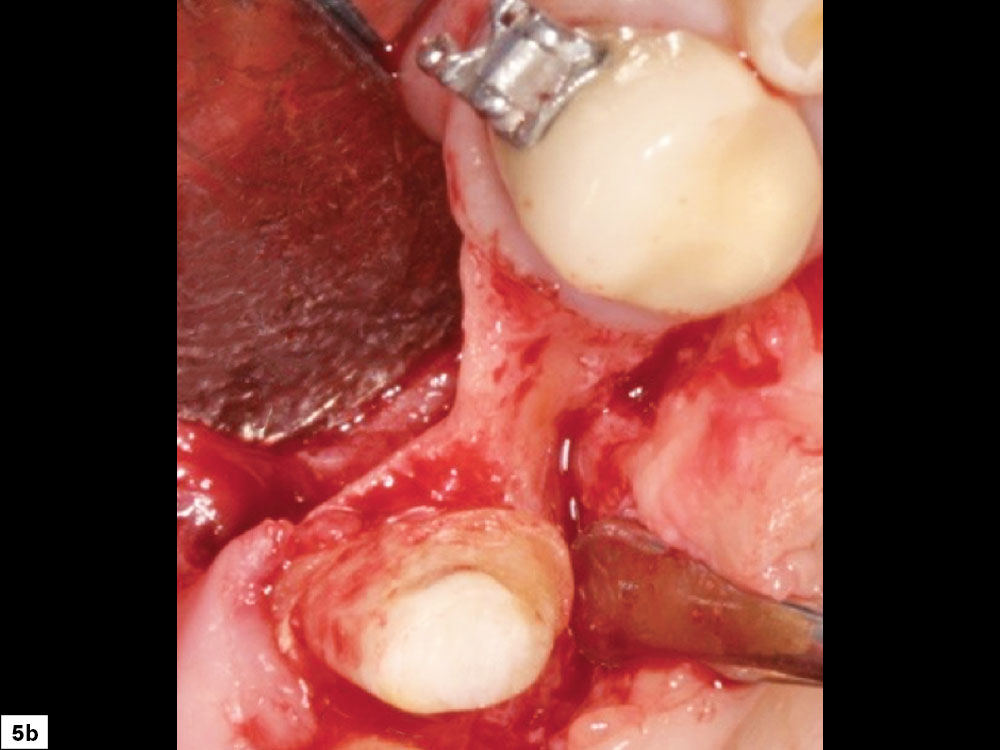

Buccal-lingual bony defects, which often occur in the anterior maxilla or anterior mandible, are extremely challenging. These anatomic areas present technical challenges with respect to tissue release, space maintenance and graft containment. However, the most common difficulty with these types of defects is placement of tenting screws, as available bone is often insufficient to obtain fixation of these important holders of the graft space. These types of defects should also be limited to clinicians with extensive surgical and bone grafting experience (Figs. 5a, 5b).

Buccal-lingual bony defect illuatration: An hourglass type of ridge morphology

Close-up of space maintenance and prevention of micromovement of the graft material

Figures 5a, 5b: Buccal-lingual bony defect: An hourglass type of ridge morphology is more complex, as grafting is indicated on the buccal and lingual aspects, and space maintenance and prevention of micromovement of the graft material are difficult.